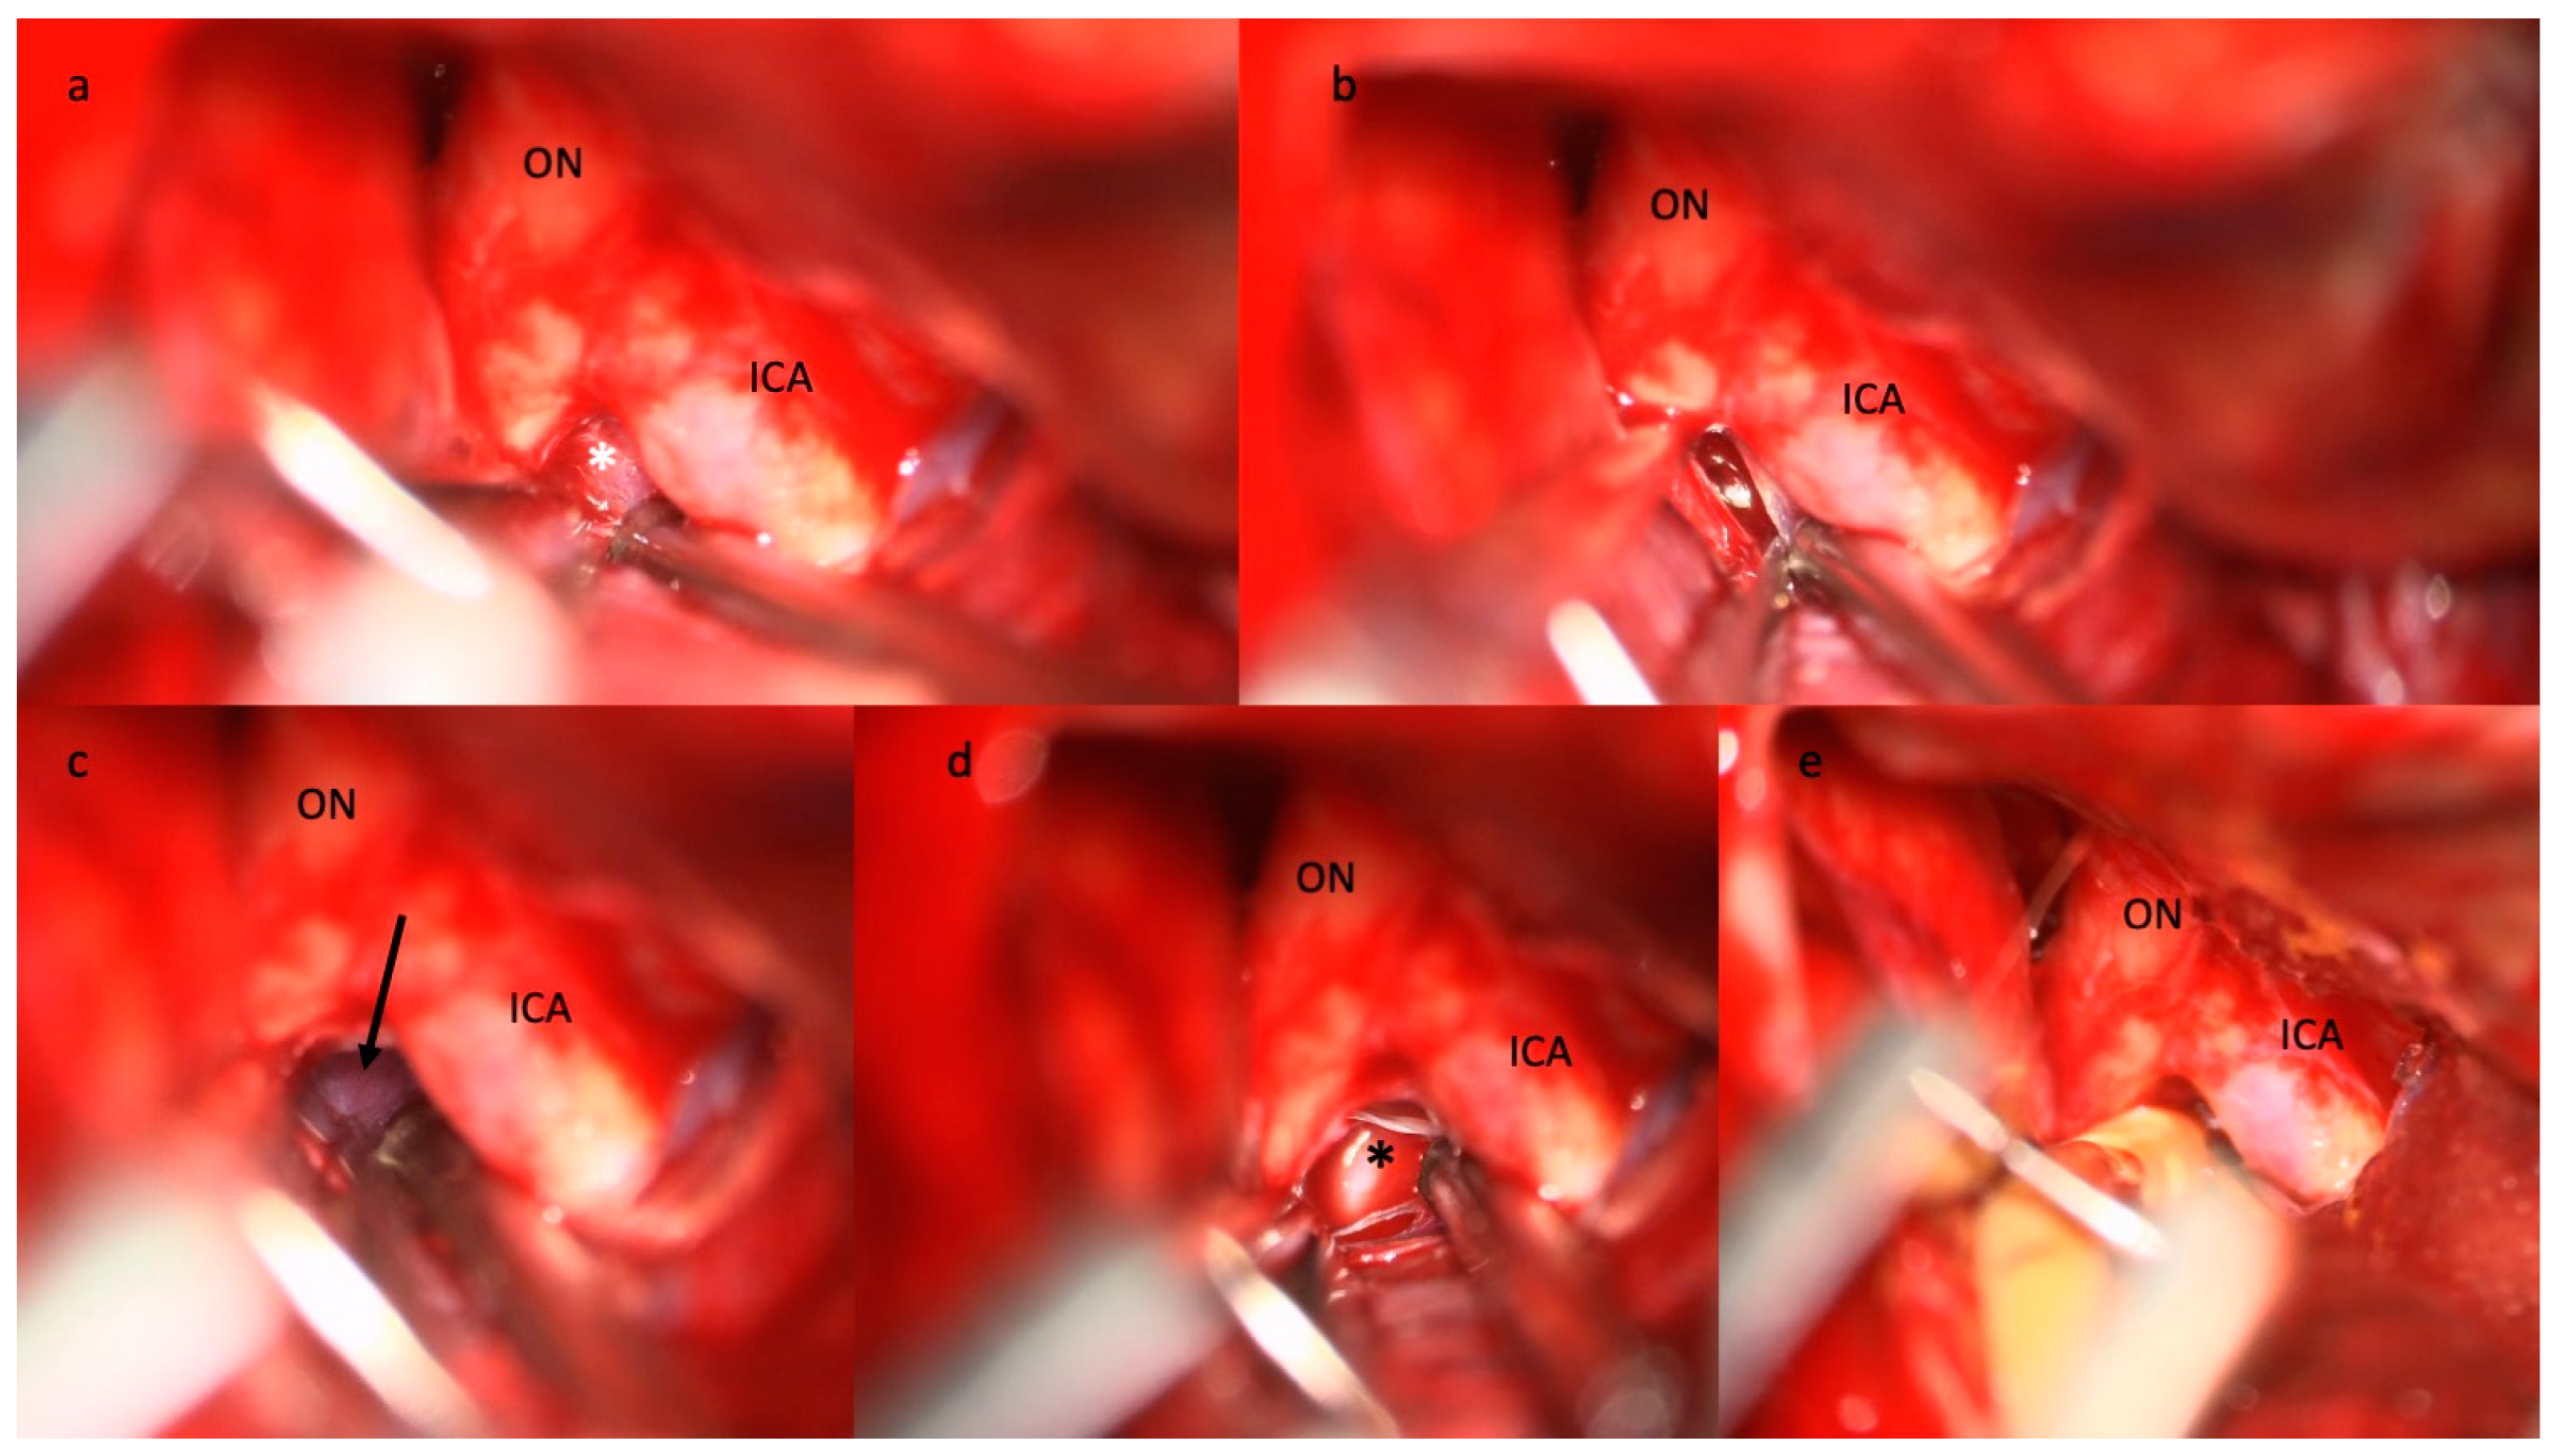

- Giammattei, L.; Starnoni, D.; Messerer, M.; Daniel, R.T. Basal Cisternostomy for Severe TBI: Surgical Technique and Cadaveric Dissection. Front. Surg. 2022, 9, 915818. [Google Scholar] [CrossRef]

- Sturiale, C.L.; Ricciardi, L.; Marchese, E.; Puca, A.; Olivi, A.; Albanese, A. Surgical Treatment of Anterior Communicating Artery Aneurysms: Hints and Precautions for Young Cerebrovascular Surgeons. J. Neurol. Surg. A Cent. Eur. Neurosurg. 2020, 81, 463–471. [Google Scholar] [CrossRef] [PubMed]

- Sturiale, C.L.; Rapisarda, A.; Marchese, E.; Puca, A.; Olivi, A.; Albanese, A. Surgical Treatment of Middle Cerebral Artery Aneurysms: Hints and Precautions for Young Cerebrovascular Surgeons. J. Neurol. Surg. A Cent. Eur. Neurosurg. 2021, 83, 75–84. [Google Scholar] [CrossRef] [PubMed]